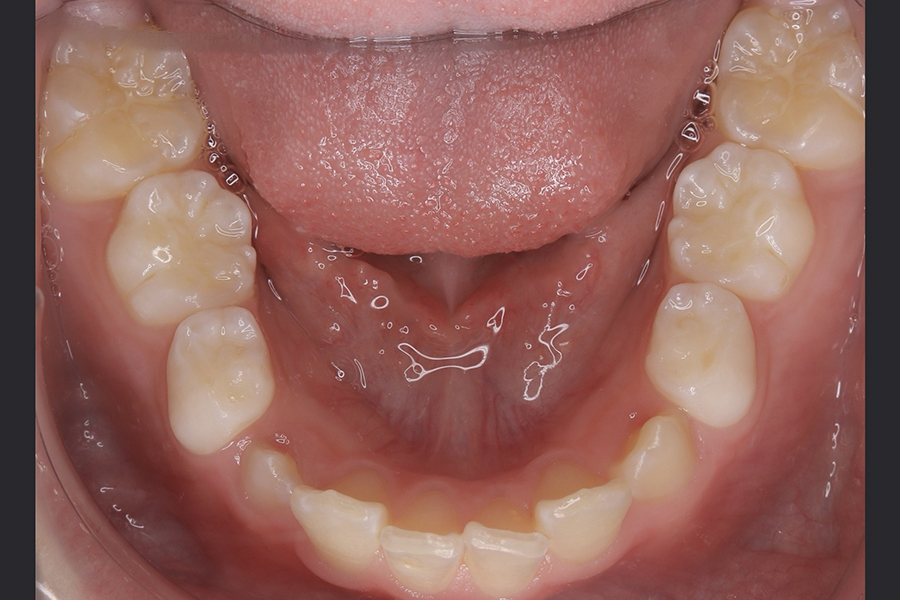

FDT症例② S.Hくん(10)

治療前

相談内容 |

うつ伏せ寝、口呼吸が気になる 歯並びの悪さ |

カウンセリング・診断結果 |

口呼吸、低位舌、上下顎劣成 |

行った治療内容 |

FDT(筋機能矯正治療/マイオブレース治療) |

治癒期間 |

2024.8.31〜 |

費用 |

385,000円(税込) |

治療リスクについて |

・お子様・保護者の協力が必要。 |

担当者からのコメント |

頑張り屋さんで真面目なHくん。正面から見ると一見綺麗ですが、横から見た時の前歯の出っ張りや永久歯の生えるスペースがないためFDTを始めました。 |